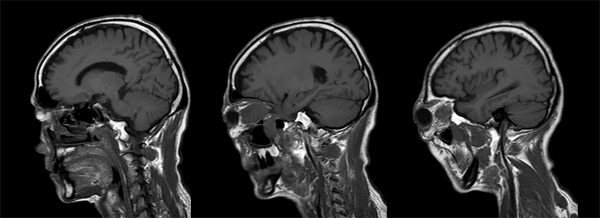

診断:下垂体炎、硬膜炎、三叉神経の炎症性偽腫瘍

【画像所見】

T1強調画像

造影後矢状断:

IgG4 計ってもらうと上昇あり

下垂体炎、硬膜炎、三叉神経の炎症性偽腫瘍